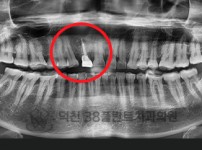

치료전후